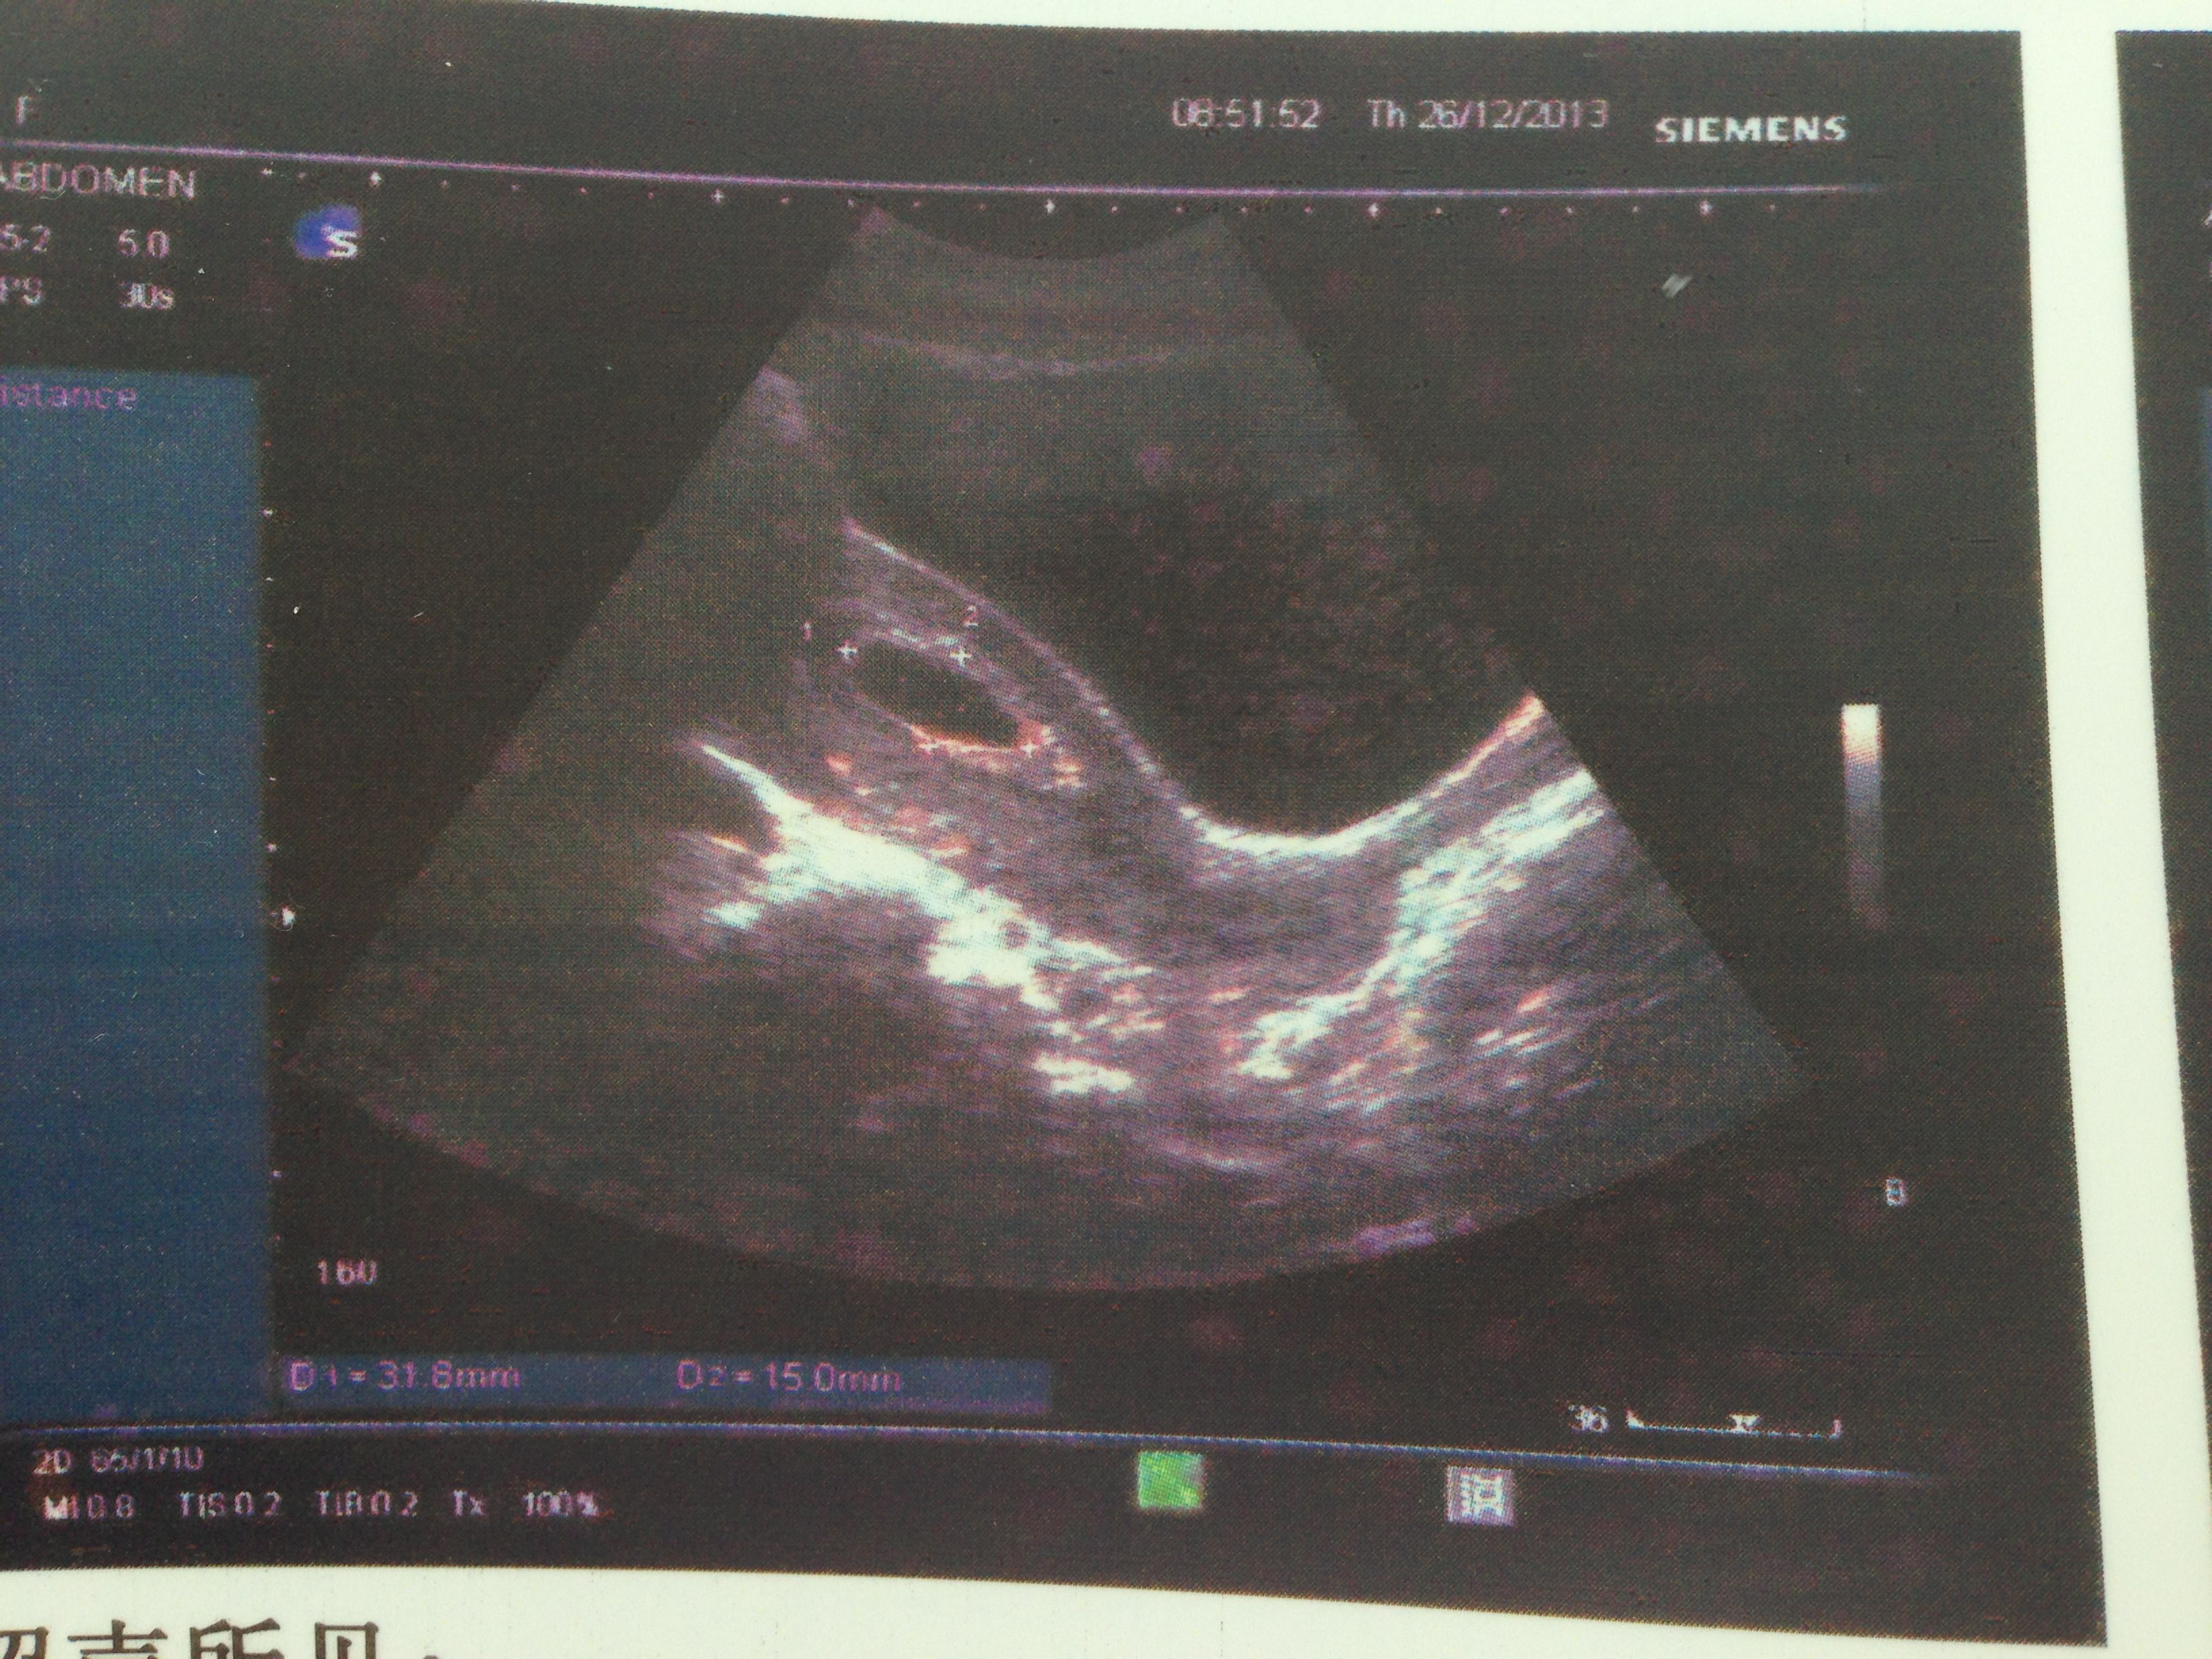

病情分析: 你好,根据你描述的情况看从检查结果看是不正常的,正常的怀孕七周就应该可以看到胎芽和胎心的。 指导意见: 现在连胎芽都没有看到的话就不正常了,建议做血液检查看看hcg的值和孕酮的值是否是正常的。希望对你有帮助,祝你健康幸福